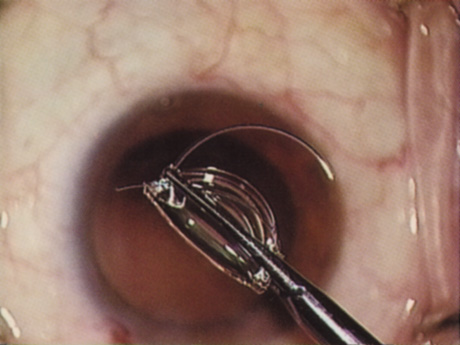

Back to Top